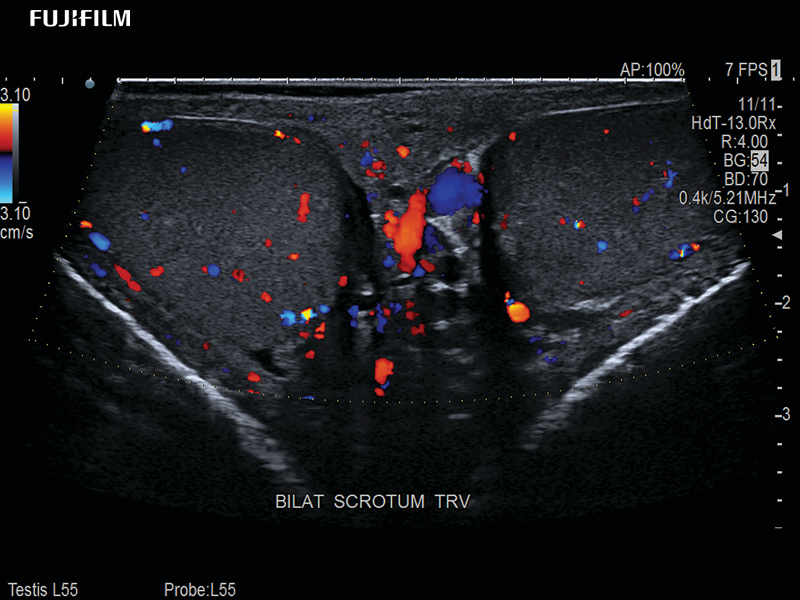

Linear transducer that is ideal for scrotal and penile doppler imaging. Trapezoid Display extends field of view and enables visualization of entire structure.